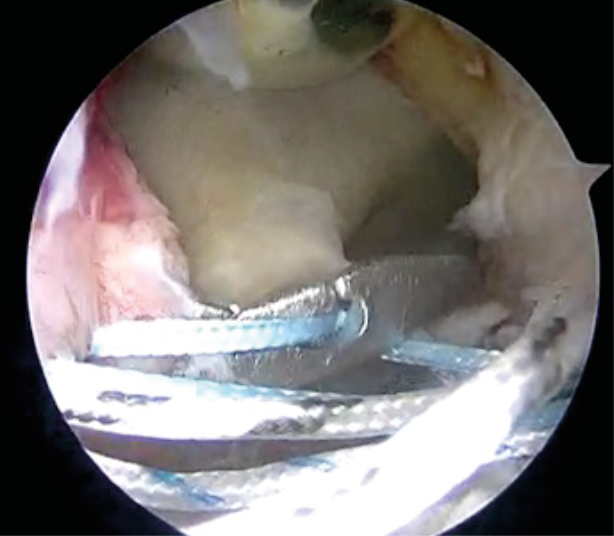

We describe here our technique of performing arthroscopic remplissage. This procedure converts Hill Sach's lesion into an extra-articular structure and acts as a checkrein against anterior translation. Patient is positioned in lateral decubitus. Posterior, antero-inferior and antero-superior portals are made. The antero-superior one is the primary viewing portal and is made more posterior than usual. After adequate viewing of HSL, it is accessed through posterior portal. External rotation of humeral head positions HSL in front of posterior cannula. The bed of the lesion is abraded and an anchor (double or triple loaded) is placed. Putting an anchor in the center of the lesion, closer to the articular surface in mediolateral plane, avoids stiffness in external rotation, post operatively (Figure 9). While passing sutures, posterior cannula should be withdrawn just outside the infraspinatus and beneath the deltoid (Figure 10). Then the sutures are passed using bird beak suture passer, staying lateral to posterior portal avoid stiffness in external rotation. (Figure 11) Then, the knot tying is completed.

For combined arthroscopic bankart repair and remplissage, we start with diagnostic arthroscopy, followed by mobilization of Bankart's lesion and preparation of the glenoid. Inferior labral suture and a 5 0'clock anchor is placed. Remplissage procedure is then performed except knot tying. Once the Bankart's repair is completed, knot tying is done for remplissage. (Figure 12)